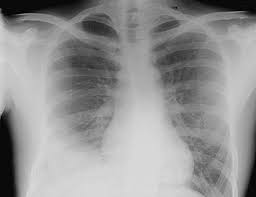

Pneumonia Dog Lung Cancer Xray / Coin Lesion Lung Radiology Reference Article Radiopaedia Org - Microbial pneumonia can be bacterial, fungal, or parasitic in nature.. The types of dog pneumonia. Primary lung cancer in dogs is relatively rare in dogs (under 1% of all cancer in dogs), but pulmonary adenocarcinoma is the most common type of canine lung cancer. Lung issues, like cancer, can be difficult to diagnose in dogs. Dog pneumonia or lung cancer. This is not to say the effects on a loved dog's body are the same as an infection.

Shutterstock Puzzlepix from image.shutterstock.com Your veterinarian may recommend an fna and cytology or a biopsy, to confirm the diagnosis, and determine exactly what kind of lung cancer is present. Bronchoscopy would also provide the opportunity to biopsy the lung and obtain mucous from the lung for. As a matter of fact, almost 80% of primary lung cancer is caused by adenocarcinoma. A retrospective study of 1011 hospitalized patients with pneumonia was undertaken to assess the value of routine convalescent chest radiography for detection of underlying lung cancer. Generally speaking, dog pneumonia falls into two categories. Your exam and imaging findings will already be abnormal if you have lung cancer. It was not on their radar that i could be dealing with lung cancer based on my age and background. So to help you differentiate between these two :

Fungal pneumonia, also called mycotic pneumonia, refers to a fungal infection of the lungs that results in pneumonia caused by breathing in one of many different fungi spores. It was not on their radar that i could be dealing with lung cancer based on my age and background. It is caused by a viral or bacterial infection in the respiratory tract. If you have lung cancer, it may be more difficult for your doctor to diagnose pneumonia. Usually involves with considering our symptoms of any illness or disease as cancer. Primary lung cancer are frequently located in the caudal (towards the hind end of the pet) lung lobes, however can be located in any lung lobe and are usually a single mass in the lungs, unless the tumor has spread. 3 doctors agree send thanks to the doctor As a matter of fact, almost 80% of primary lung cancer is caused by adenocarcinoma. Pneumonia is an inflammatory conditi. Signs of the primary tumors in dogs. You can spend a lot of money on invasive diagnostic tests like bronchoalveolar lavage … and never really know exactly what the cause is. Pneumonia is an infection of lung tissue usually caused by viruses, bacteria, fungi, and/or parasites.however, bacteria and viruses cause the majority of pneumonia infections. Pneumonia and lung cancer both affect the lungs but one is easily treatable and the other is potentially life threatening.

Common Pulmonary Diseases In Dogs Clinician S Brief from files.brief.vet A retrospective study of 1011 hospitalized patients with pneumonia was undertaken to assess the value of routine convalescent chest radiography for detection of underlying lung cancer. Signs of the primary tumors in dogs. Fungal pneumonia, also called mycotic pneumonia, refers to a fungal infection of the lungs that results in pneumonia caused by breathing in one of many different fungi spores. Primary lung cancer are frequently located in the caudal (towards the hind end of the pet) lung lobes, however can be located in any lung lobe and are usually a single mass in the lungs, unless the tumor has spread. Pneumonia caused by aspiration, on the other hand, happens when a dog inhales foreign particles into the lungs. Typical signs of bacterial pneumonia include fever, difficulty breathing, lethargy and coughing. Your exam and imaging findings will already be abnormal if you have lung cancer. The fungi will travel through the dog's circulatory system and lymph nodes, causing severe coughing, breathing trouble, and a viscous phlegm in the nose and throat.

In both cases, you may have. The fungi will travel through the dog's circulatory system and lymph nodes, causing severe coughing, breathing trouble, and a viscous phlegm in the nose and throat. As these can also be caused by other disease, diagnostics include a full physical exam, blood work, radiographs, and may also require bronchoscopy with. If you have lung cancer, it may be more difficult for your doctor to diagnose pneumonia. Here's why cancer can look like an infection: This, in turn, may cause collapse of the air sacs surrounding the tumor. Typical signs of bacterial pneumonia include fever, difficulty breathing, lethargy and coughing. A definitive diagnosis of lung cancer requires a sample of tissue (biopsy). These are microbial pneumonia and aspiration pneumonia. Bacterial pneumonia is an inflammation of the lung usually caused by bacterial or viral infection but can be caused by inhalation of an irritant. This is not to say the effects on a loved dog's body are the same as an infection. Primary lung cancer are frequently located in the caudal (towards the hind end of the pet) lung lobes, however can be located in any lung lobe and are usually a single mass in the lungs, unless the tumor has spread. Pneumonia and lung cancer both affect the lungs but one is easily treatable and the other is potentially life threatening.

Pneumonia Management In Dogs And Cats Veterinary Partner Vin from veterinarypartner.vin.com Typical signs of bacterial pneumonia include fever, difficulty breathing, lethargy and coughing. Pneumonia caused by aspiration, on the other hand, happens when a dog inhales foreign particles into the lungs. It was not on their radar that i could be dealing with lung cancer based on my age and background. Microbial pneumonia can be bacterial, fungal, or parasitic in nature. Malignant tumors trigger inflammation in surrounding normal lung tissue, and they may obstruct your airways and interfere with normal airflow. Lung issues, like cancer, can be difficult to diagnose in dogs. Signs of the primary tumors in dogs. Pneumonia in dogs can have different causes:

Primary lung cancer are frequently located in the caudal (towards the hind end of the pet) lung lobes, however can be located in any lung lobe and are usually a single mass in the lungs, unless the tumor has spread. In both cases, you may have. X rays are very helpful in the diagnosis of lung cancer in dogs. Primary lung cancer are frequently located in the caudal (towards the hind end of the pet) lung lobes, however can be located in any lung lobe and are usually a single mass in the lungs, unless the tumor has spread. If you have lung cancer, it may be more difficult for your doctor to diagnose pneumonia. Pneumonia caused by aspiration, on the other hand, happens when a dog inhales foreign particles into the lungs. Lung issues, like cancer, can be difficult to diagnose in dogs. Your veterinarian may recommend an fna and cytology or a biopsy, to confirm the diagnosis, and determine exactly what kind of lung cancer is present. Pneumonia is an infection of lung tissue usually caused by viruses, bacteria, fungi, and/or parasites.however, bacteria and viruses cause the majority of pneumonia infections. These are microbial pneumonia and aspiration pneumonia. Primary lung cancer in dogs is relatively rare in dogs (under 1% of all cancer in dogs), but pulmonary adenocarcinoma is the most common type of canine lung cancer. My dog had pneumonia come on quickly this last august, we took her to the local er at 3am when we noticed her breathing labored and strange behavior. Common things are common ,pneumonia is lot common than lung cancer ,get an xray in 6 weeks it should clear up by then.